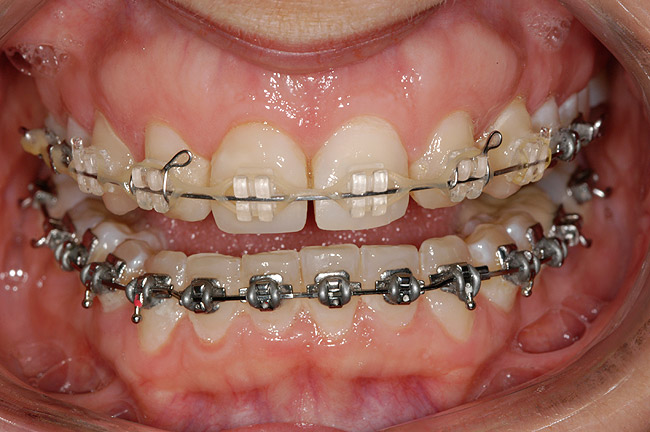

Figure 3 Additional orthodontic treatment is initiated to improve the dental midline and evenly distribute the space around the microdontic lateral incisors.

Figure 3

Figure 4 The dental midline is in improved harmony with the facial midline following the second round of orthodontic treatment.